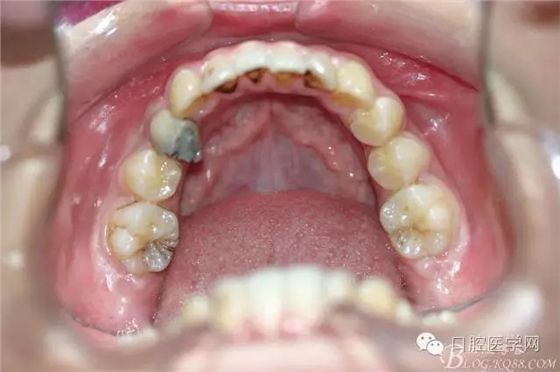

患者,女,13歲。要求矯治排齊上下前牙。

正畸查:替牙合。第一恒磨牙中性合。上牙弓尖圓型下牙弓方圓型。前牙覆合3度覆蓋7.5mm。下前牙咬到上舌側(cè)牙齦。上頜擁擠4.0mm,下頜擁擠

3.0mm。上頜稍前突下頜后縮,上下唇前突,上前牙覆蓋下唇,下唇外翻。面下三分之一過短,頦唇溝明顯,開唇露齒,頦饜窩明顯。顳下頜關(guān)節(jié)開閉口無彈響,無壓痛,開口型開口度正常。